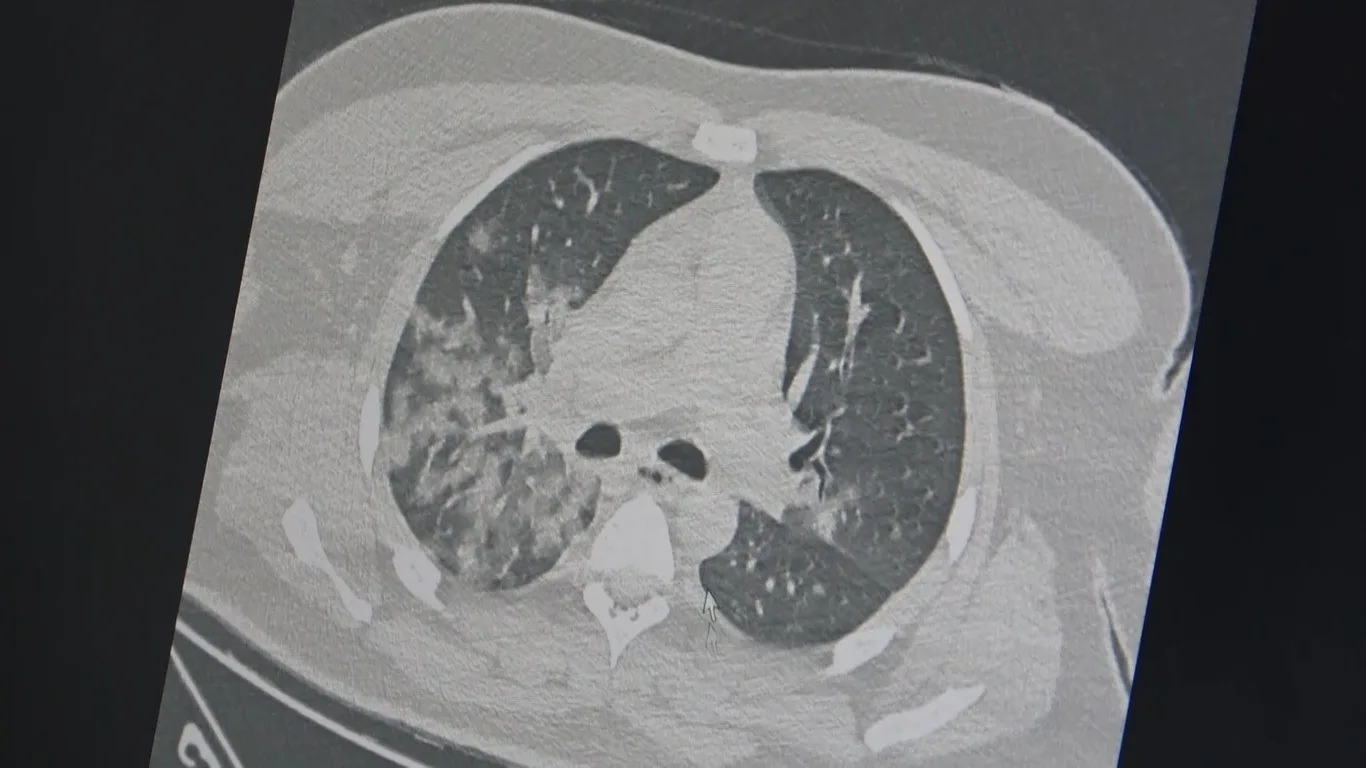

Kovid-19 salgını sonrası özellikle acil servislerde genç hastalarda ani ölümle sonuçlanan akciğer ve kalp/damar hastalıklarında ciddi artış olduğunu ifade eden Göğüs Hastalıkları Uzmanı Prof. Dr. Şevket Özkaya, açıklamalarda bulundu. Özkaya, “Tüm dünyada en çok sorulan soru, bu artan ani ölümlerin sebebi kovid-19 aşıları mı yoksa korona virüsünün etkileri mi? Bu soru İngiltere’de 46 milyon kişi üzerinde yapılan bir araştırma ile netleşti. Kovid-19 aşılarının damar tıkanıklığı sonucu kalp krizi ve inme riskini azalttığını bildirildi. Vücudumuzda damar tıkanıklığı gelişmesinde ve akciğer, kalp ve beyin damarlarında ölümle sonuçlanan olaylara neden olan 3 temel faktör vardır. Damar iç duvarında (endotel) hasar; ameliyat, hastalık veya uzun süre seyahat sebebiyle vücudumuzun hareketsiz kalması, pıhtılaşmaya yatkınlık yapan genetik ve ilaç kullanımı (doğum kontrol hapları vb). Bu 3 faktörden en önemlisi olan damar iç duvarı (endotel) hasarı olup, kovid-19 virüsü ile enfekte olan bir kişide virüs yüküne bağlı gelişen özellikle ’sitokin’ fırtınası başta olmak üzere, kan plazmasının toksik ve tahrip edici damar iç duvarında ciddi hasar yapıyor, pıhtı oluşumunun ilk aşaması gerçekleşiyor. Ayrıca hastalık veya uzun süre seyahat sebebiyle vücudumuzun hareketsiz kalması ile pıhtı oluşumuna neden oluyor ve ölümcül sonuçlar ile karşılaşıyoruz. Özellikle gençlerin kovid-19 sonrası bozulmuş damar yapısı, ağır egzersiz ve spor ile ölümcül kalp krizlerine neden oluyor” diye konuştu.

“Aşılar özellikle salgın döneminde insan vücudundaki virüs yükünü azaltarak, hem hastalığın ağır geçirilmesine hem de kan plazmasının damar iç duvarındaki bu harap edici etkisini azaltıyor. Buna bağlı damar tıkanıklıklarını da azalttığı ve akciğer, kalp ve beyin damarlarındaki ölümcül tıkanıklarını da azalttığını düşünüyoruz. Sonuç olarak, ani artan genç ölümlerinden kovid-19 aşıları değil, kovid-19 virüsünün damar hasarına yaptığı hasar nedeniyle olduğu kanıtlanmış oldu” şeklinde konuştu.